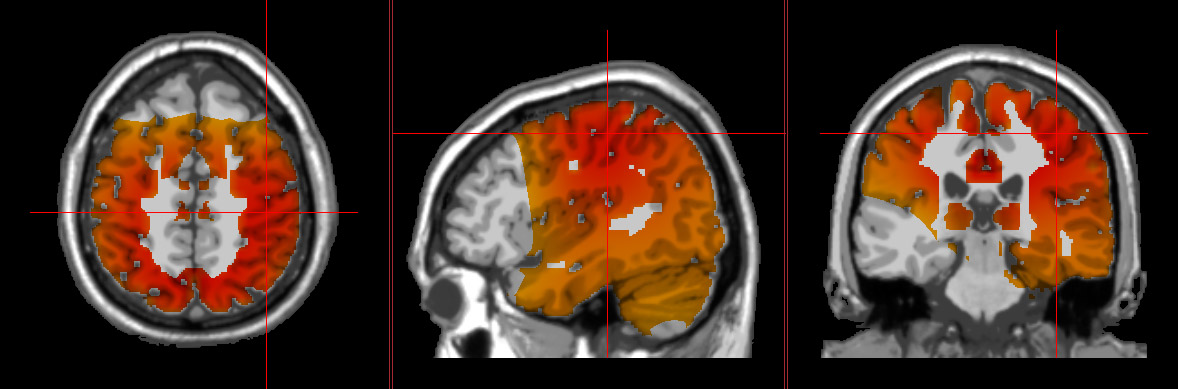

QEEG showing signs of stress loreta neurofeedback showing typical signs of chronic stress chronic stress shown in the brain by loreta neurofeedback

At NeuroGrove, the first step of any treatment package is a comprehensive assessment that includes QEEG brain mapping, LORETA 3D neuroimaging, various testing, and a thorough discussion of symptoms and goals. This allows us to assess for the brain patterns and physiological symptoms most commonly associated with chronic stress.